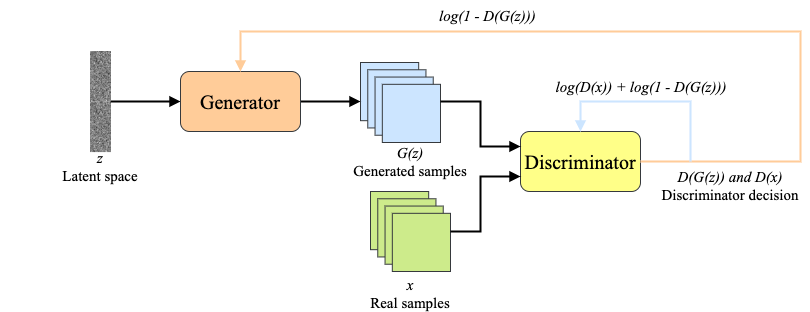

A promising avenue to solve this problem is the usage of Generative Adversarial Networks (GANs) to generate additional images that will increase the size of training datasets. A GAN is a class of unsupervised learning where two networks (generator and discriminator) are joined by a feedback loop to compete with each other. As a result, the generator constantly learns how to better deceive the discriminator, on the other hand, the discriminator gets constantly better at detecting synthetic images.

A promising avenue to solve this problem is the usage of Generative Adversarial Networks (GANs) as an oversampling technique to solve problems with class imbalance. Generative Adversarial Network - is a class of deep learning framework designed by Ian Goodfellow and his colleagues Goodfellow et al. (2014). The main idea of GANs is a competitive process between two neural networks - a generator and a discriminator. The generator is trying to deceive the discriminator by producing images similar to the ones from the original dataset. On the other hand, the main target of the discriminator is to distinguish real data from the generated (fake) one. As a result, the generator constantly learns how to better fool the discriminator, on the other hand, the discriminator gets constantly better at detecting synthetic images. A typical GAN architecture is presented in Fig. 1.